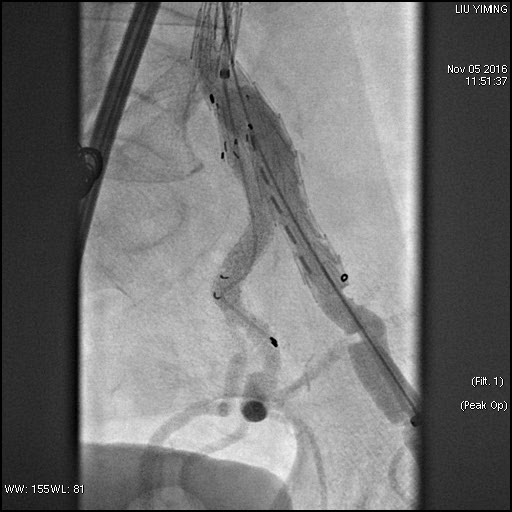

其中,在复杂主动脉病变腔内修复术应用手术直播中,郭伟教授带领其团队使用彩神在线网信彩票-彩神通免费版下载-彩神8争霸vlll-彩神购彩购彩大厅-彩神软件陆立根免费版-彩神ll争霸3-彩神ll彩神8-彩神ll争霸彩票-拼搏在线彩神网网页版科技公司的髂动脉分叉支架系统(IBD)以完全腔内重建的方式成功修复复杂腹主动脉瘤及髂动脉瘤。该例手术患者为64岁的男性,被诊断为肾下腹主动脉瘤,瘤体最大直径约6.5cm,双侧髂动脉瘤。患者成功植入彩神在线网信彩票-彩神通免费版下载-彩神8争霸vlll-彩神购彩购彩大厅-彩神软件陆立根免费版-彩神ll争霸3-彩神ll彩神8-彩神ll争霸彩票-拼搏在线彩神网网页版科技IBD支架,定位准确,无内漏,成功保留了左侧髂内动脉,术后造影显示髂内动脉通畅。

图:术前造影、术中造影、术后造影